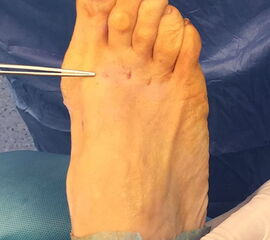

Das hier vorgestellte Konzept beruht auf den grundsätzlichen Überlegungen von Sharma, unter Anwendung der Prinzipien der minimalinvasiven Fußchirurgie. Die Korrektur der Adduktionsfehlstellung der Metatarsalia II bis IV erfolgt über eine modifizierte, lateralisierende, distale, minimalinvasive Metatarsale-Osteotomie (DMMO) (interner Link: OP Technik DMMO). Die Osteotomie der Metatarsalia II bis IV ohne Osteosynthese erlaubt eine limitierte Verlagerung der Metatarsaleköpfchen nach kranial, was ein etabliertes Verfahren zur Therapie einer Metatarsalgie darstellt 7. Eine zusätzliche, im Normalfall unerwünschte Lateralverschiebung der Metatarsaleköpfchen kann bei einem Pes adductus zur Korrektur genutzt werden. Verglichen zu offenen Therapieverfahren ermöglicht dieses Konzept die Korrektur der Adduktionsstellung der Metatarsalia II bis IV bei minimiertem Weichteiltrauma und verkürzter die OP-Dauer. Persönliche Erfahrungen mit dem Verfahren deuten darüber hinaus auf ein geringeres postoperatives Schmerzniveau, eine einfachere Mobilisierbarkeit und eine hohe kosmetische Zufriedenheit hin.

Das hier vorgestellte Verfahren umfasst die Kombination verschiedener etablierter Konzepte, die sich zur Korrektur eines des Pes adductus mit Hallux valgus Deformität in besonderer Weise eignen. Dabei wird eine offene Lapidus Arthrodese mittels winkelstabiler plantarer Platte mit verschiedenen perkutanen distalen Eingriffen zur Korrektur der Pes adductus Fehlstellung kombiniert 8910.

Zum Lesen der Bildbeschreibung und zur Vollansicht bitte die Bilder anklicken.